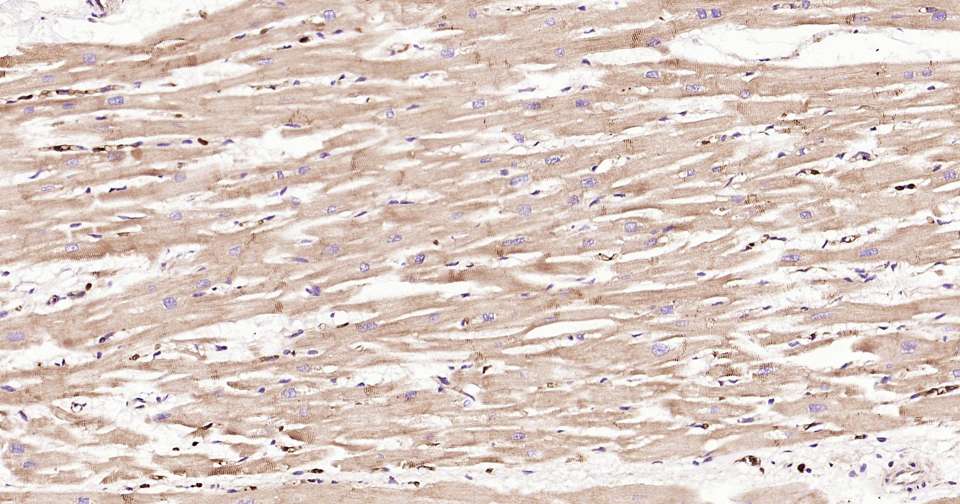

Immunohistochemical analysis of paraffin embedded human heart tissue slide using IHC0336H (Human APAF1 Kit).